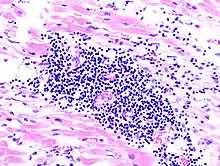

Virale Myokarditis

Mikro: Interstitielles lymphozytäres Infiltrat (kleine blaue Zellen), kaum Nekrosen.

![]() Virale Myokarditis bei Patient mit plötzlichem kongestiven Herzversagen, Autopsiepräparat, H&E. |

![]() idem. |